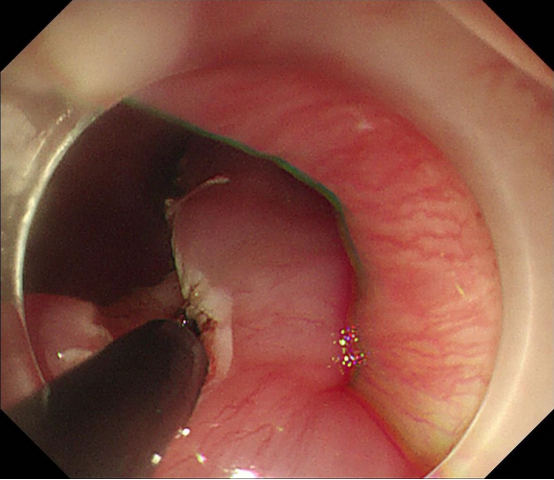

经过和患者及家属详细沟通后,胡兵教授团队制定了详细的手术方案,2025年1月15日,手术正式进行。在内镜引导下,胡兵教授利用高频电刀先切开病变基底部周边黏膜,进入黏膜下层,再逐步剥离病变基底部。由于病变太大,通过常规内镜下圈套器套住病变取出的方法力量太小,难以将病变全部取出,胡兵教授巧妙应用了外科手术中使用的卵圆钳将已经拖出体外的病变部分夹住后将全部病变顺利取出。40分钟后,胡兵教授完整切除了巨大包块,且术中出血量少(图1、图2、图3)。术后病变测量大小约22.0*5.5cm(图4)。病理检查显示为巨大纤维血管息肉。

(图3)